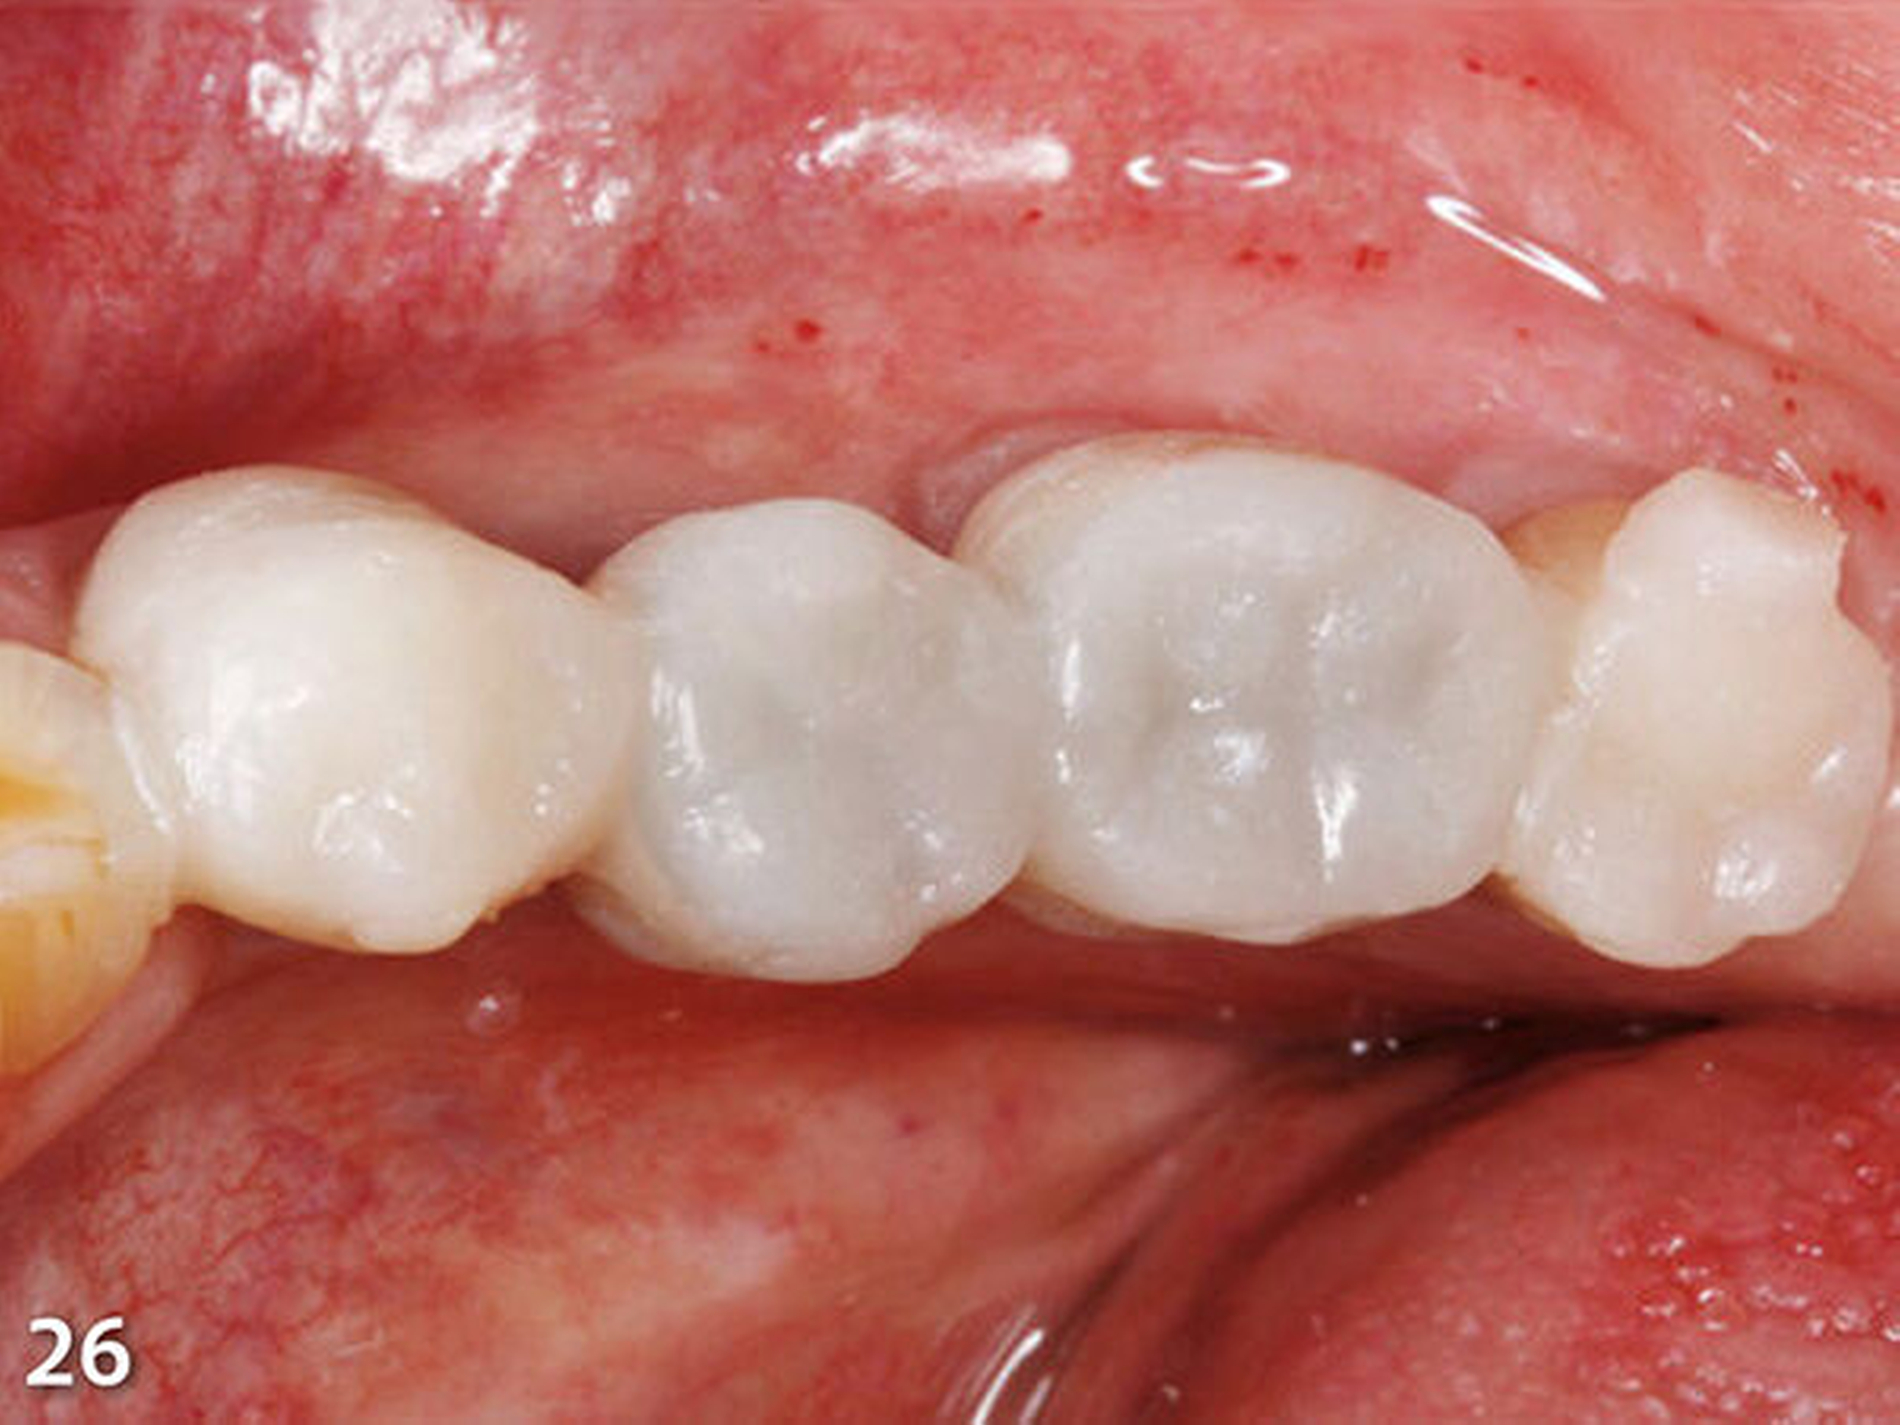

Nach dem bündigen Verschleifen der bukkalen und oralen Einspritz- und Entlüftungskanäle wurde die zweite Übertragungsschiene (Schiene 2), die ebenfalls im Frontbereich geteilt wurde, eingebracht, nachdem der damit zu rekonstruierende endständige Molar zuvor silikatisiert, silanisiert und mit Adhäsiv vorbehandelt worden war (Abb.25). Die Abstützung dieser Schablone erfolgte an den gerade zuvor im ersten Schritt aufgebauten, anterior liegenden Seitenzähnen. Der Aufbau der Kaufläche wurde wieder nach der zuvor beschriebenen Methode ausgeführt (Abb.26).